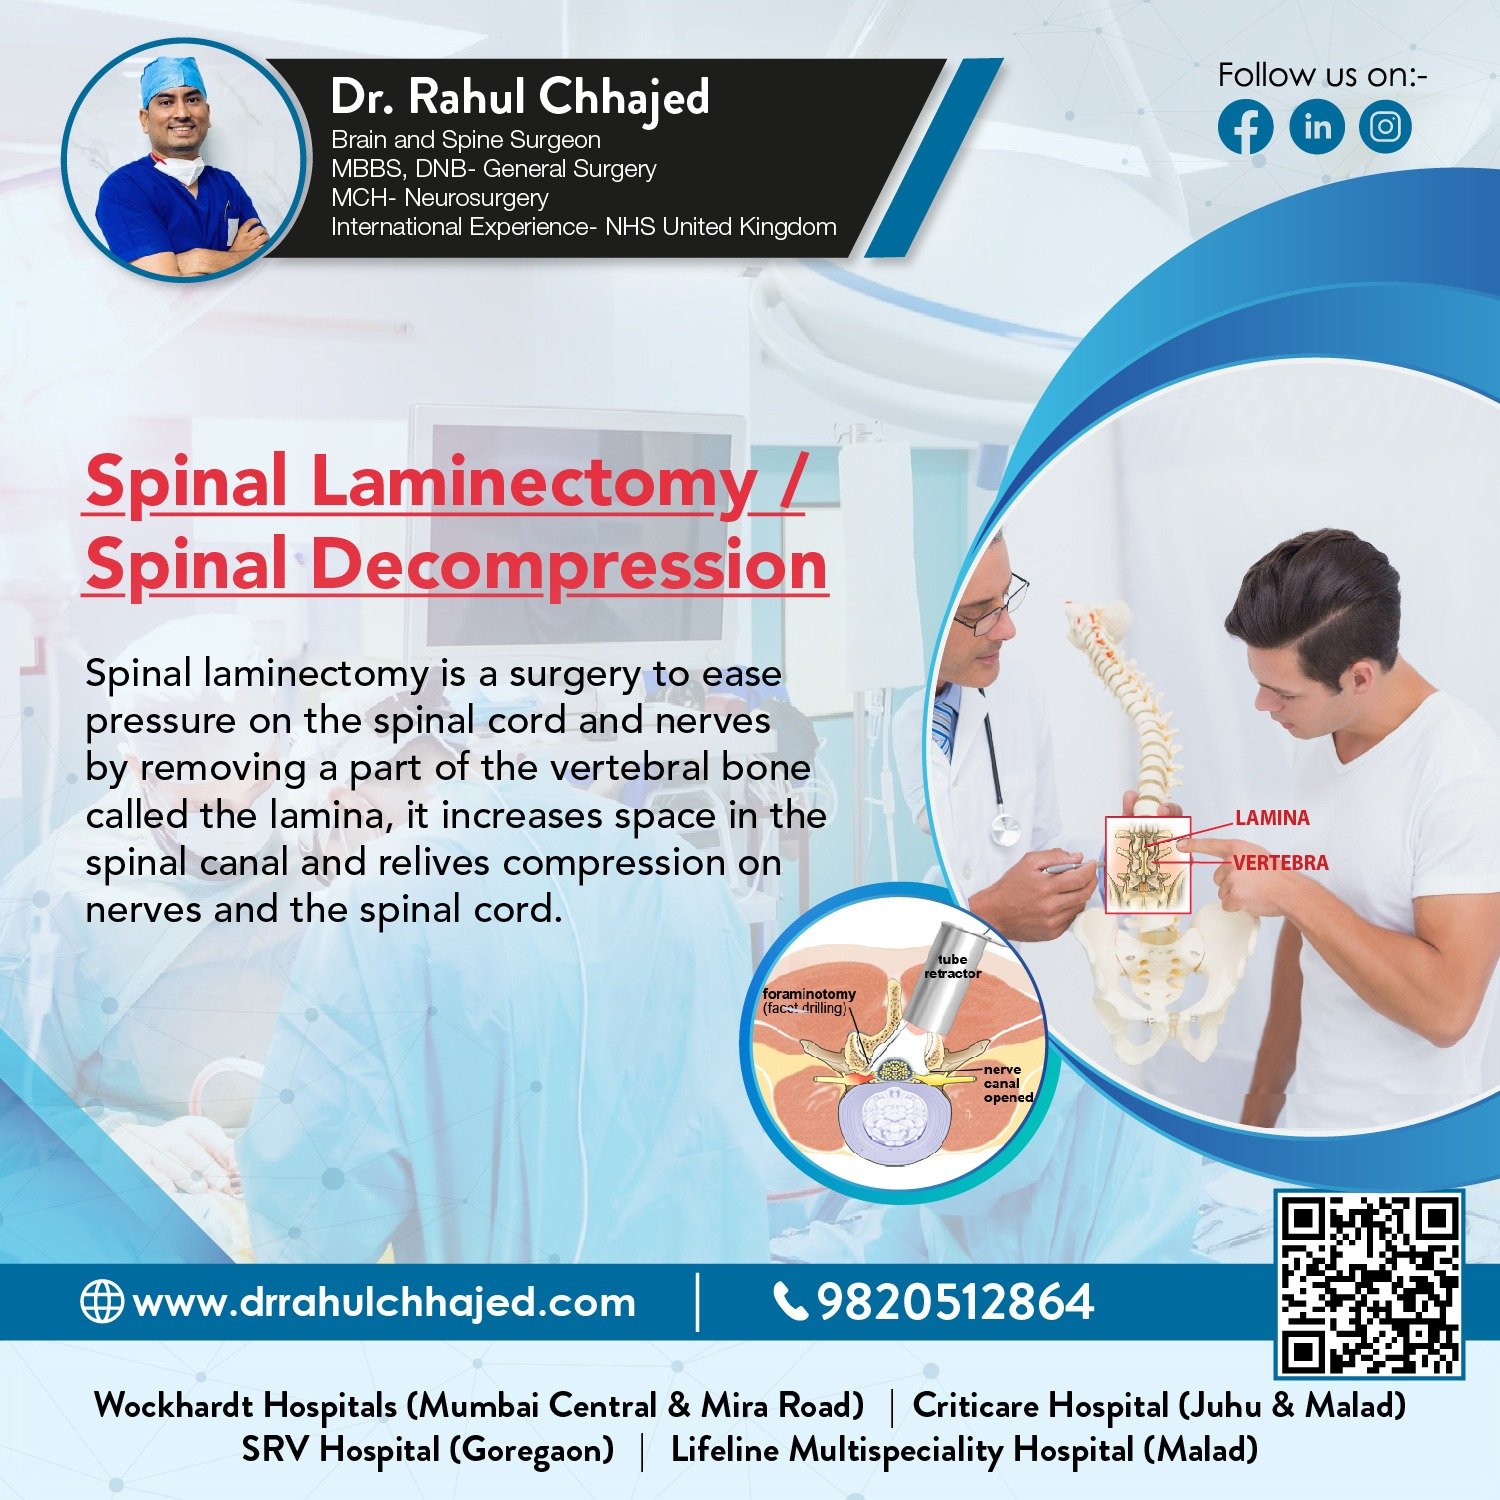

Spine Surgery

Dr. Rahul is a highly experienced spine surgeon specializing in diagnosing and treating spinal conditions. He performs a wide range of surgical options for spinal conditions, including minimally invasive techniques, spinal fusion, and disc replacement.

Minimal invasive spine surgery / endoscopic spine surgery

Endoscopic spine surgery offers many benefits over traditional open surgery, including smaller incisions, less blood loss, and faster recovery times. Dr. Rahul is the go-to specialist for endoscopic spine surgery in the area.